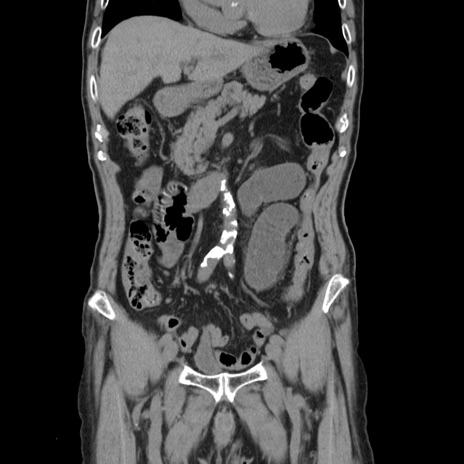

症例24(冠状断像)

【症例】80歳代男性

【主訴】左側腹部痛、嘔吐

【現病歴】本日早朝より左腹部に痛みあり。昼頃嘔吐認めたため、救急要請。

【既往歴】直腸癌(Mile手術)、胆摘

【身体所見】意識清明、BT 35.9℃、BP 221/93mmHg、SpO2 97%(RA) 、腹部:左ストーマ周囲に限局性の腹部膨隆あり。 膨隆部自発痛・圧痛あり・軟。

【データ】WBC 7700、CRP 0.09